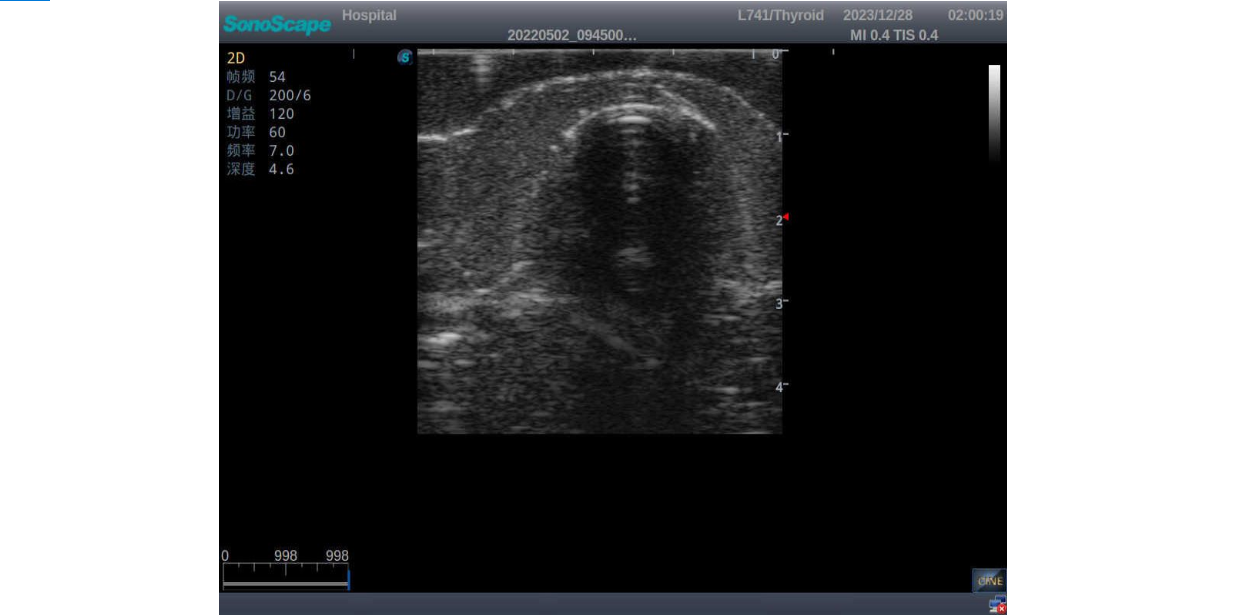

3)       It comes with four (4) thyroid modules and can show five (5) ultrasonic images: normal thyroid, thyroid adenoma, thyroid cancer, nodular goiter, thyroid cyst

Thyroid adenoma with well-defined border and smooth uniform halo

Thyroid cyst, which fluid area, dark and echo-free area can be seen